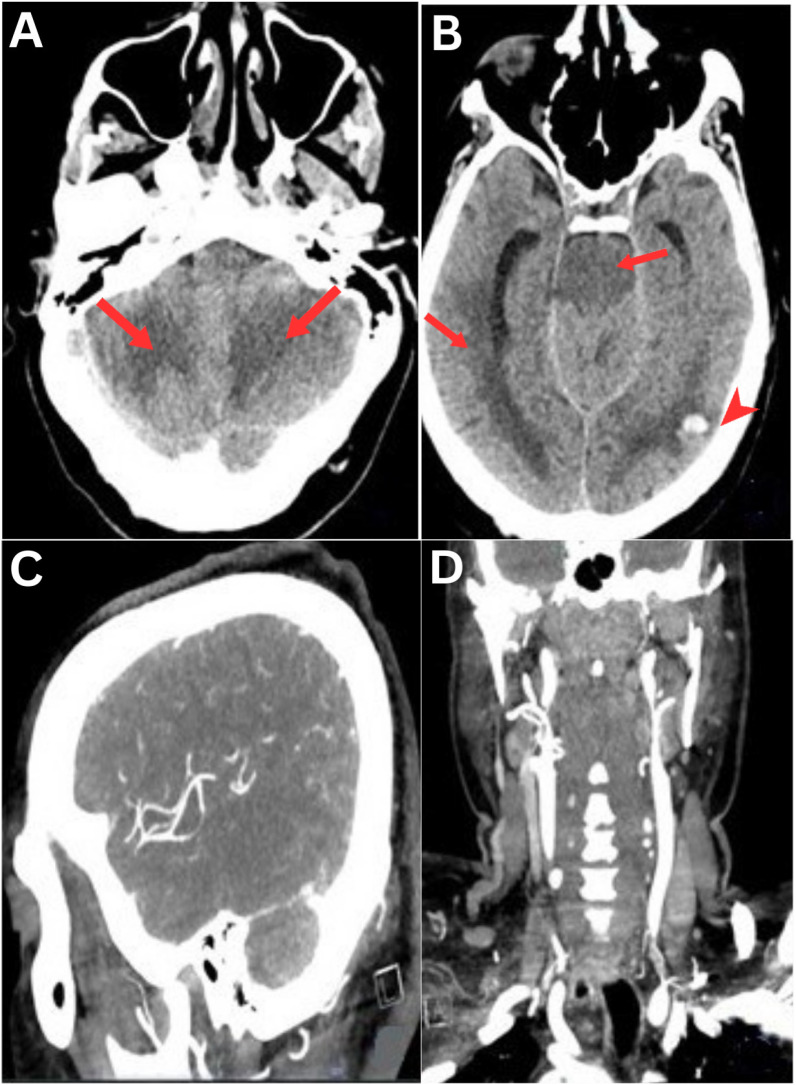

抗中性粒细胞细胞质抗体(ANCA)相关血管炎(AAV)通常表现为全身性血管炎。以间叶脑炎和周围神经病变的形式累及中枢神经系统的AAV是极为罕见的。我们报告了一位59岁男性患者,他于2024年在阿曼马斯喀特的一家三级保健医院就诊。他有亚急性的感觉改变、多发性脑神经麻痹和共济失调,并有3个月的双侧足下垂史。脑成像提示蛛网膜下腔和脑实质内出血的间膜脑炎。神经传导研究显示感觉运动轴索神经病。血管炎表现为核周anca阳性,神经活检提示血管性神经病。静脉注射类固醇并维持利妥昔单抗。他的神经功能减退,双侧足下垂。

The anti-neutrophil cytoplasmic antibody (ANCA)-associated vasculitis (AAV) usually manifests as systemic vasculitis. AAV with central nervous system involvement in the form of mesenrhombencephalitis and peripheral neuropathy is extremely rare. We report a 59-year-old male patient who presented to a tertiary care hospital in Muscat, Oman, in 2024. He had a subacute presentation of altered sensorium, multiple cranial nerve palsy and ataxia with 3 months history of bilateral foot drop. Brain imaging was suggestive of mesenrhombencephalitis with subarachnoid and intraparenchymal haemorrhage. Nerve conduction studies revealed sensorimotor axonal neuropathy. Vasculitis profile showed perinuclear-ANCA positivity and the nerve biopsy was suggestive of vasculitic neuropathy. He was treated with intravenous steroids and maintained on rituximab. His neurological deficits improved with residual bilateral foot drop.